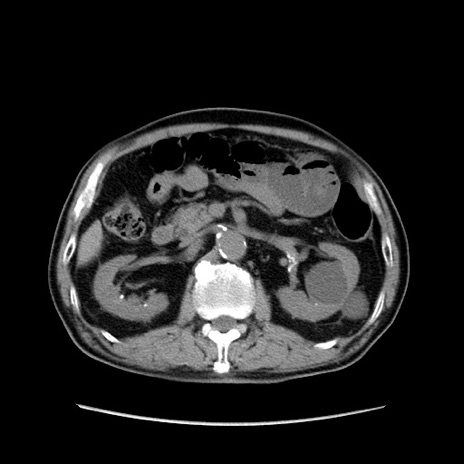

症例24(横断像)

【症例】80歳代男性

【主訴】左側腹部痛、嘔吐

【現病歴】本日早朝より左腹部に痛みあり。昼頃嘔吐認めたため、救急要請。

【既往歴】直腸癌(Mile手術)、胆摘

【身体所見】意識清明、BT 35.9℃、BP 221/93mmHg、SpO2 97%(RA) 、腹部:左ストーマ周囲に限局性の腹部膨隆あり。 膨隆部自発痛・圧痛あり・軟。

【データ】WBC 7700、CRP 0.09